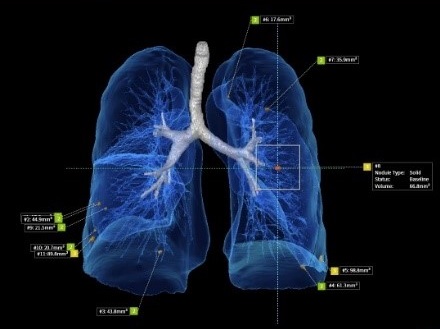

64排CT輻射劑量僅傳統CT的1/6~1/10,640切CT輻射劑量更低,完全非侵入性,可偵測出0.1公分以上的病灶。在早期肺癌篩檢上,精確度更優於MRI(僅能偵測0.5公分以上可疑病灶),可偵測早期肺癌。

為提供完整醫療服務,永越引進超世代新型─Canon (Aquilion ONE PRISM) CT640,全景式多能譜AI電腦斷層掃描儀;掃描更快、範圍更大、輻射劑量更低,內建獨家AI人工智能的影像重建系統 (AiCE)及影像判斷分析軟體,搭配全自動劑量調控技術,更優異精細的超高品質影像,讓病灶無所遁形。

這麼快的速度使得大部分受檢者不必服用藥物來降低心跳以進行心臟檢查,並具有更加清晰的影像品質,可應用於心血管疾病,腫瘤篩檢,以及其他全身應用。憑藉卓越的影像品質,幫助醫生準確診斷,進而給患者及時的治療。低輻射劑量、低顯影劑用量、大範圍一次性動態成像,配載獨家獨家AI人工智能軟體,可同時檢查多器官疾病等特點,且由於放射線對人體的損傷減少,檢查速度提高,檢查舒適度也大為改善;對受檢民眾是一大福音。